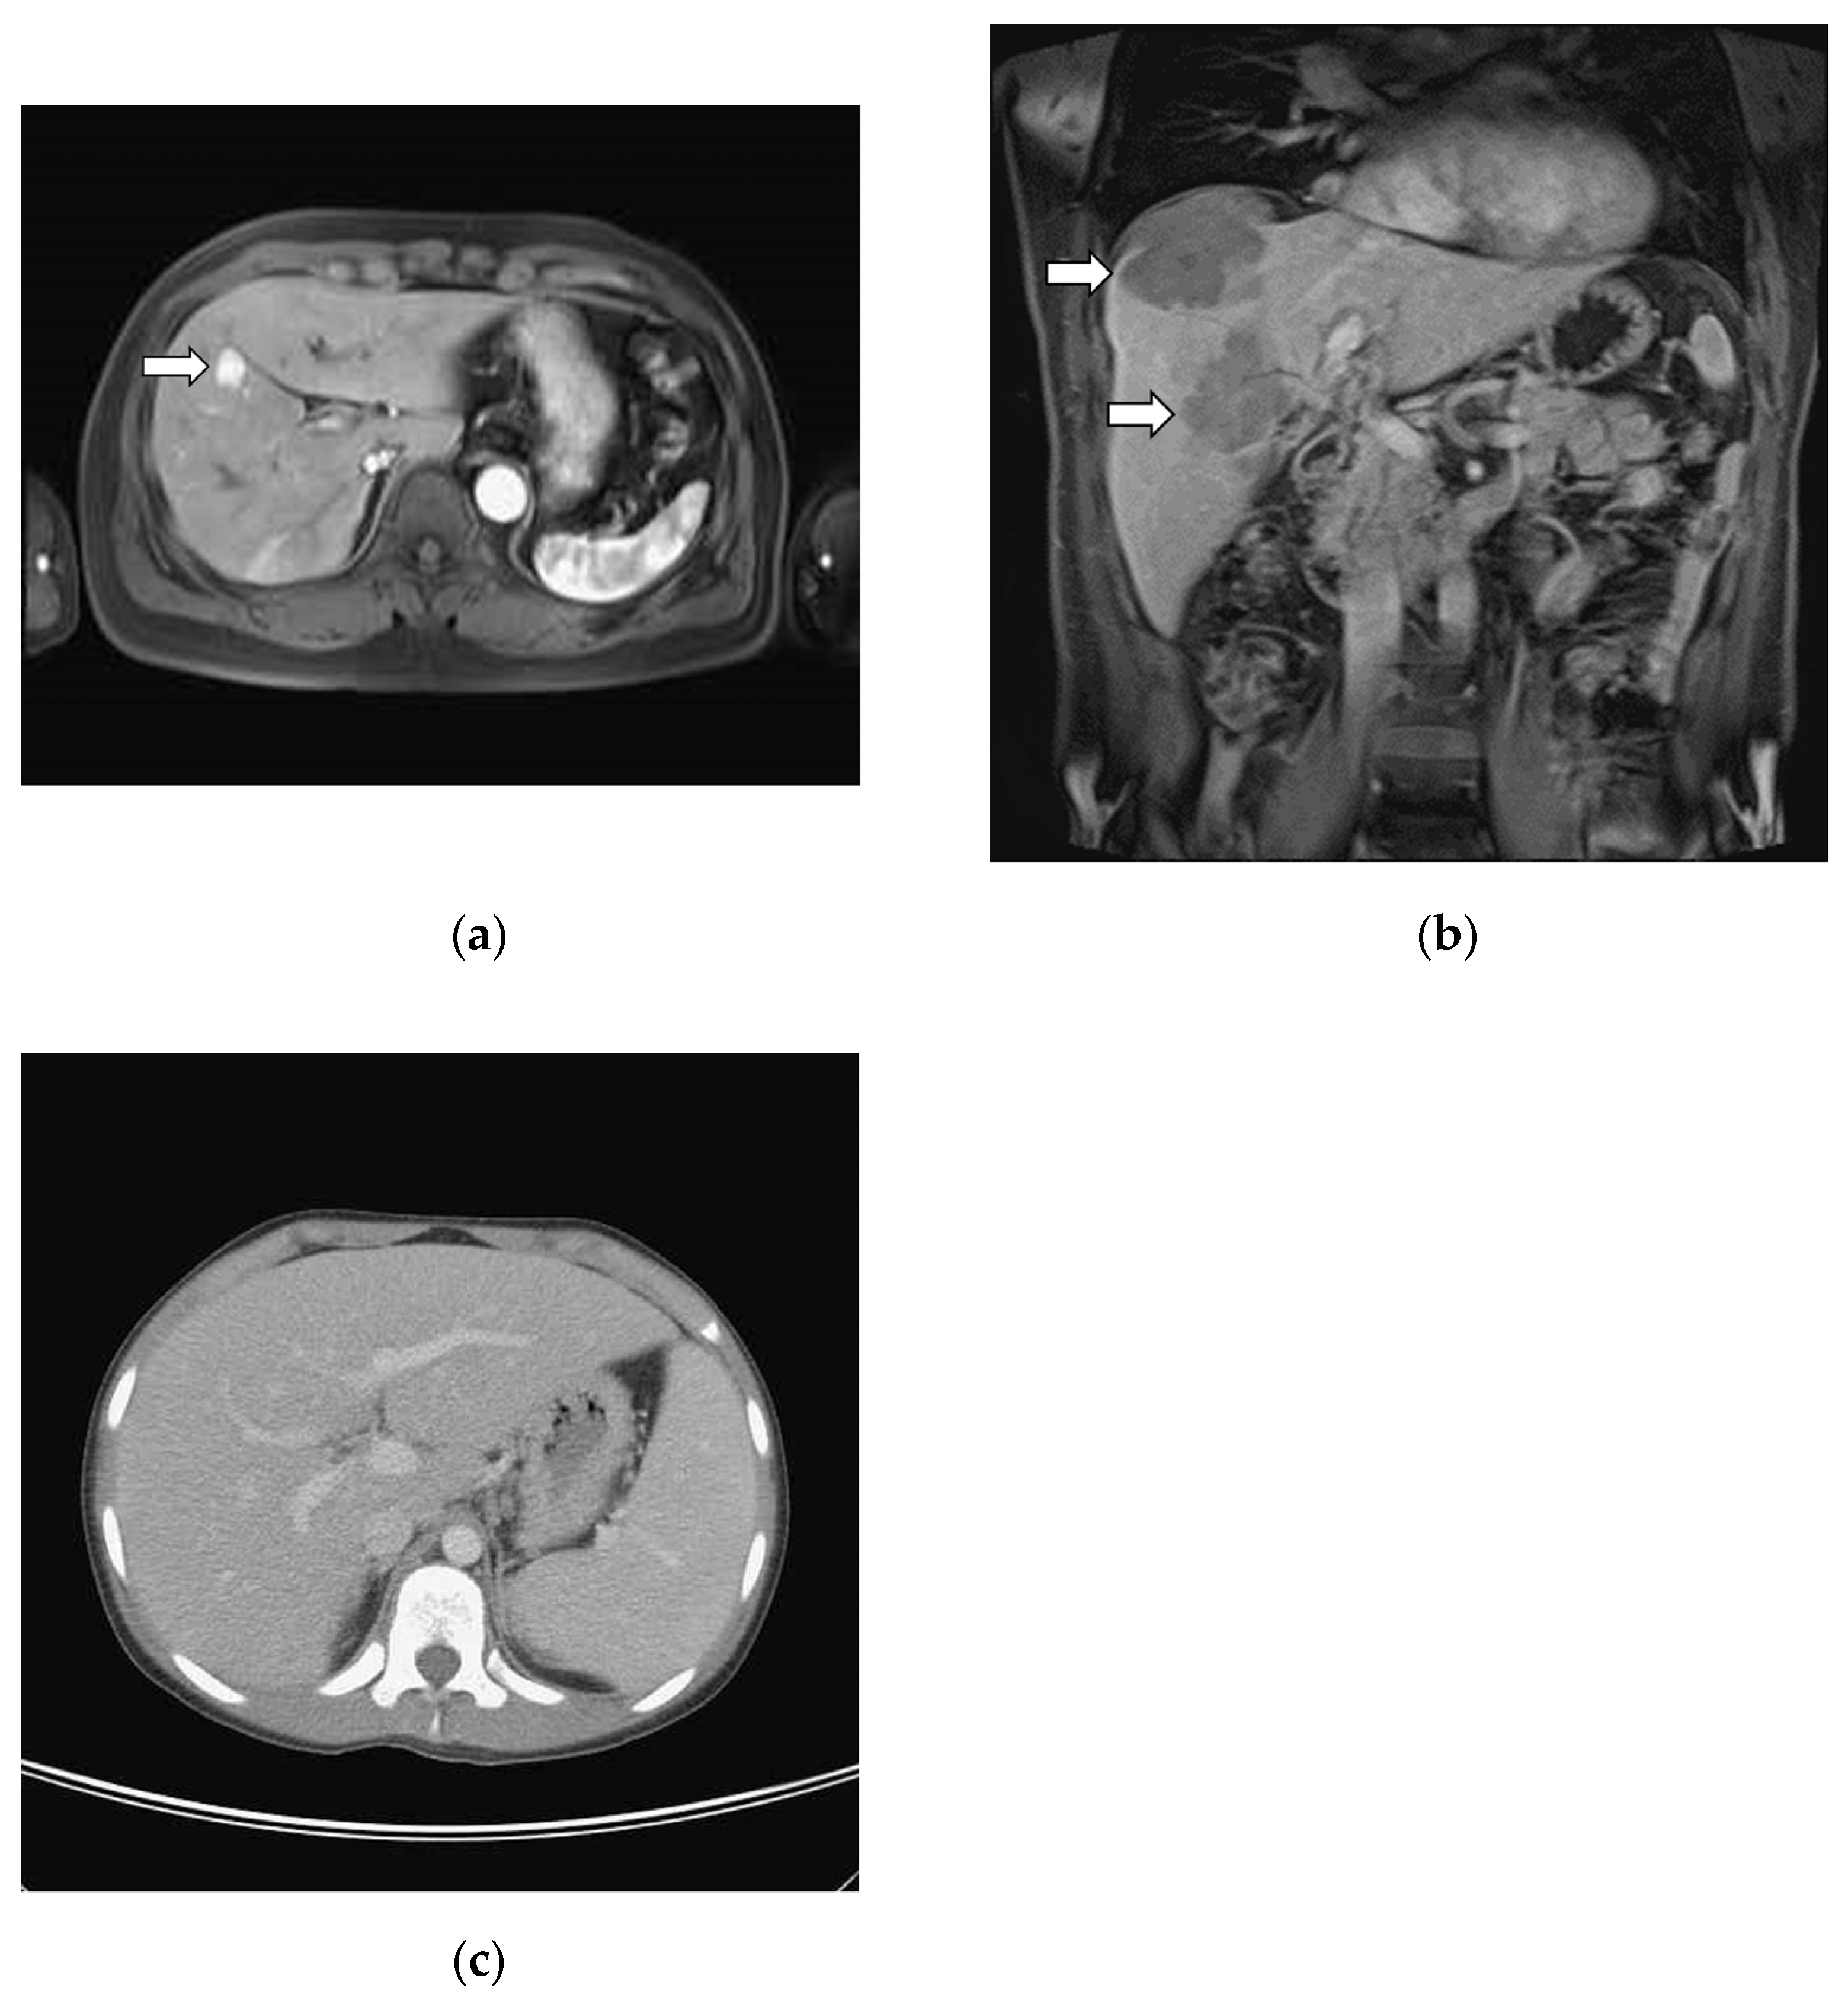

3.2. Image Studies

| Image Findings a | PHL | (n = 6) | SHL | (n = 29 #) |

|---|---|---|---|---|

| Mass lesion | ||||

| Single mass | 33% | (2/6) | 7% | (2/29) |

| Multiple masses | 50% | (3/6) | 66% | (19/29) |

| Non-mass lesion | ||||

| Hepatomegaly | 0% | 0 | 14% | (4/29) |

| Negative image findings | 17% | (1/6) | 14% | (4/29) |